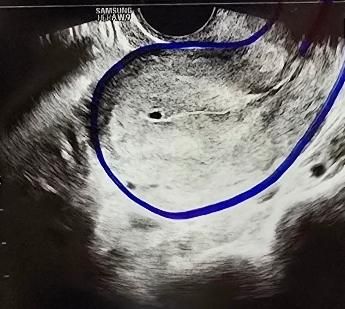

5주째 6주째 비교해서 아기집 크기가 차이없어서 계유유산 판정을 받았어요. 그런데 5주 사진보다 6주 사진이 내막도 얇아진거 같고 아기집도 자궁 아래쪽으로 내려온거 같은데 자연배출을 기다려도 될까요? 수술을 해야할까요?

6주6일차와 5주6일차(파란줄있는 사진)입니다

• 2번 째 사진